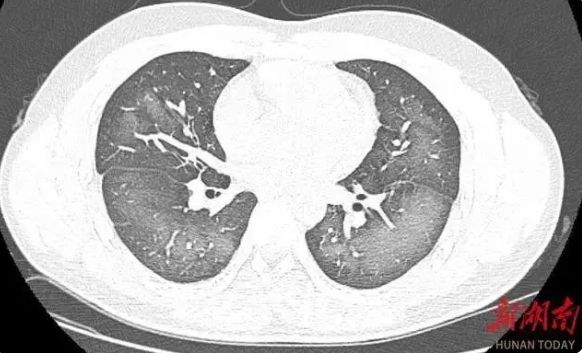

中国湖南长沙一20岁男生李林(化名)近日在外出前使用了防晒喷雾,在对著面部喷洒时一不小心误吸,随即出现胸闷、咳嗽的症状。症状一直持续到第二天仍未好转,他急忙来到湖南省长沙市第三医院就诊。经检查,肺部CT片显示,李林双肺居然呈现大范围白色样病变,报告提示“白肺”。

据《新湖南》客户端报道,“白肺”一般是指重症肺炎在X线或CT检查下的表现,患者肺部呈现一大片的白色状态,往往会出现呼吸困难、呼吸衰竭,严重者还会出现其他脏器功能障碍。

长沙市第三医院放射影像科的接诊医师表示,吸入有害物质如粉尘、喷雾等,也可导致肺部出现大范围白色样病变。这名年轻的患者就是因为使用不当,吸入了一部分防晒产品进入肺部,导致“白肺”的发生。

急诊医生给予吸氧、化痰、抗感染等相关治疗后,李林症状得到明显改善。(《新湖南》照片)